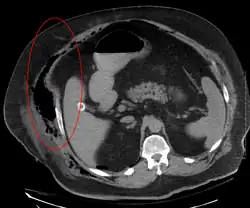

Necrotizing fasciitis is ideally a clinical diagnosis based on symptoms. Due to the need for rapid surgical treatment, the time delay in performing imaging is a major concern.[15] Hence, imaging may not be needed if signs of a necrotizing infection are clear. However, due to the vague symptoms associated with the earlier stages of this disease, imaging is often useful in clarifying or confirming the diagnosis.[15]

Both CT scan and MRI are used to diagnose NF, but neither are sensitive enough to rule out necrotizing changes completely.[2]

Computed tomography (CT)

If available, computed tomography (CT) is the most convenient tool in diagnosing NF due to its speed and resolution (detects about 80% of NF cases).[16] CT scan may show fascial thickening, edema, or abscess formation.[2][15] CT is able to pick up on gas within tissues better than MRI, but it is not unusual for NF to present without gas on imaging.[15] In addition, CT is helpful in evaluating complications due to NF and finding possible sources of infections.[15] Its use may be limited in pregnant patients and patients with kidney issues.[15]

Magnetic resonance imaging (MRI)

Magnetic resonance imaging (MRI) is considered superior to computed tomography (CT) in the visualization of soft tissues and is able to detect about 93% of NF cases.[15] It is especially useful in finding fluid in the deep fascia, which can distinguish between NF and cellulitis.[15] When fluid collects in the deep fascia, or thickening or enhancement with contrast, necrotizing fasciitis should be strongly suspected. However, MRI is much slower than CT and not as widely available.[15] There may also be limitations on its use in patients with kidney problems.[15]